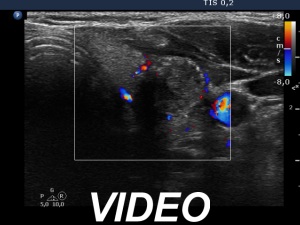

Ultrasonography. The thyroid was echonormal. There was a dominantly hypoechoic nodule in the left lobe. The nodule had both microcalcifications and macrocalcification and was avascular.